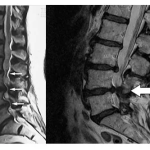

Omurga Kırıkları ve Felç Nasıl Tespit Edilir?

Omurga kırıklarını kesin olarak tespit etmek için çeşitli muayene ve görüntüleme teknikleri kullanılmaktadır. Röntgen, MR, nörolojik muayene ardından kesin tanı konabilecektir. Kırık şüphesi olan bireyler en yakın sağlık kuruluşuna başvurmalıdır.